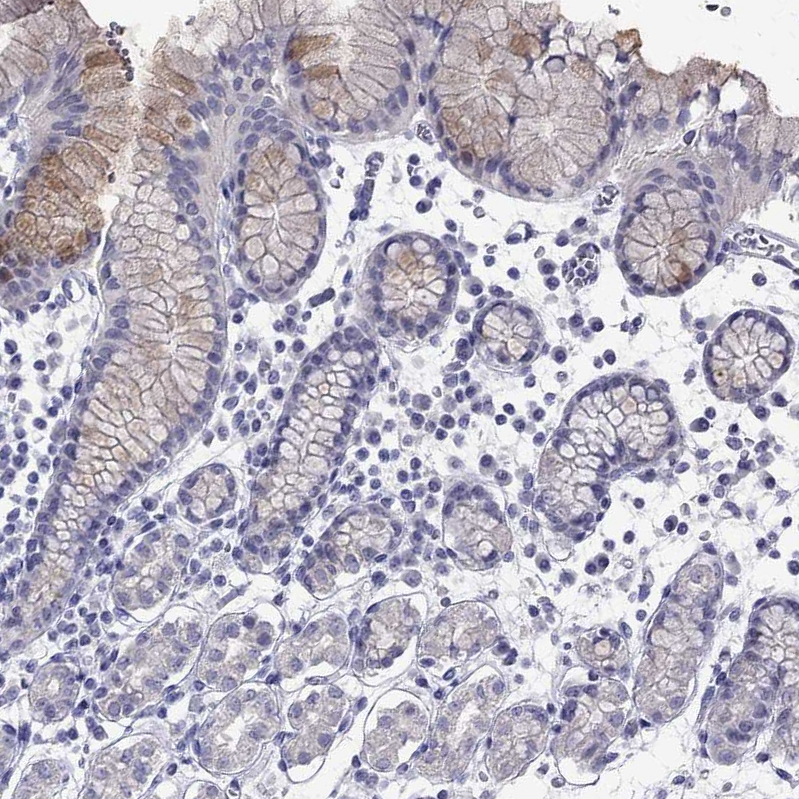

Immunohistochemical staining of human breast shows moderate cytoplasmic positivity in glandular cells.